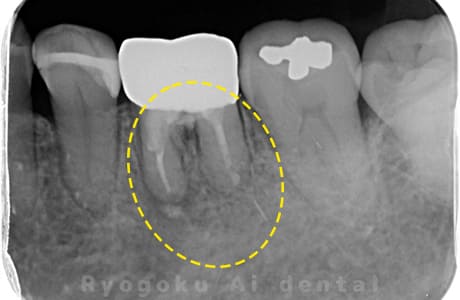

Case10

-

- 原因

- 右上6番パーフォレーション

- 治療内容

- マイクロエンド治療(パーフォレーションリペア)、ゴールドクラウン修復

- 治療費用

- 297,000円

右上奥歯を他院で抜歯と言われ、残して欲しいとのことでご来院された患者様です。穴が空いている部分をMTAでリペアを行い、再度マイクロスコープ下で根管治療を行い、ゴールドクラウンで修復しました。経過も良好で、大変満足して頂けました。

<リスク・副作用>

術後は痛み、腫れ、痺れなどの副作用が生じる場合があります。症状が再発する可能性があります。